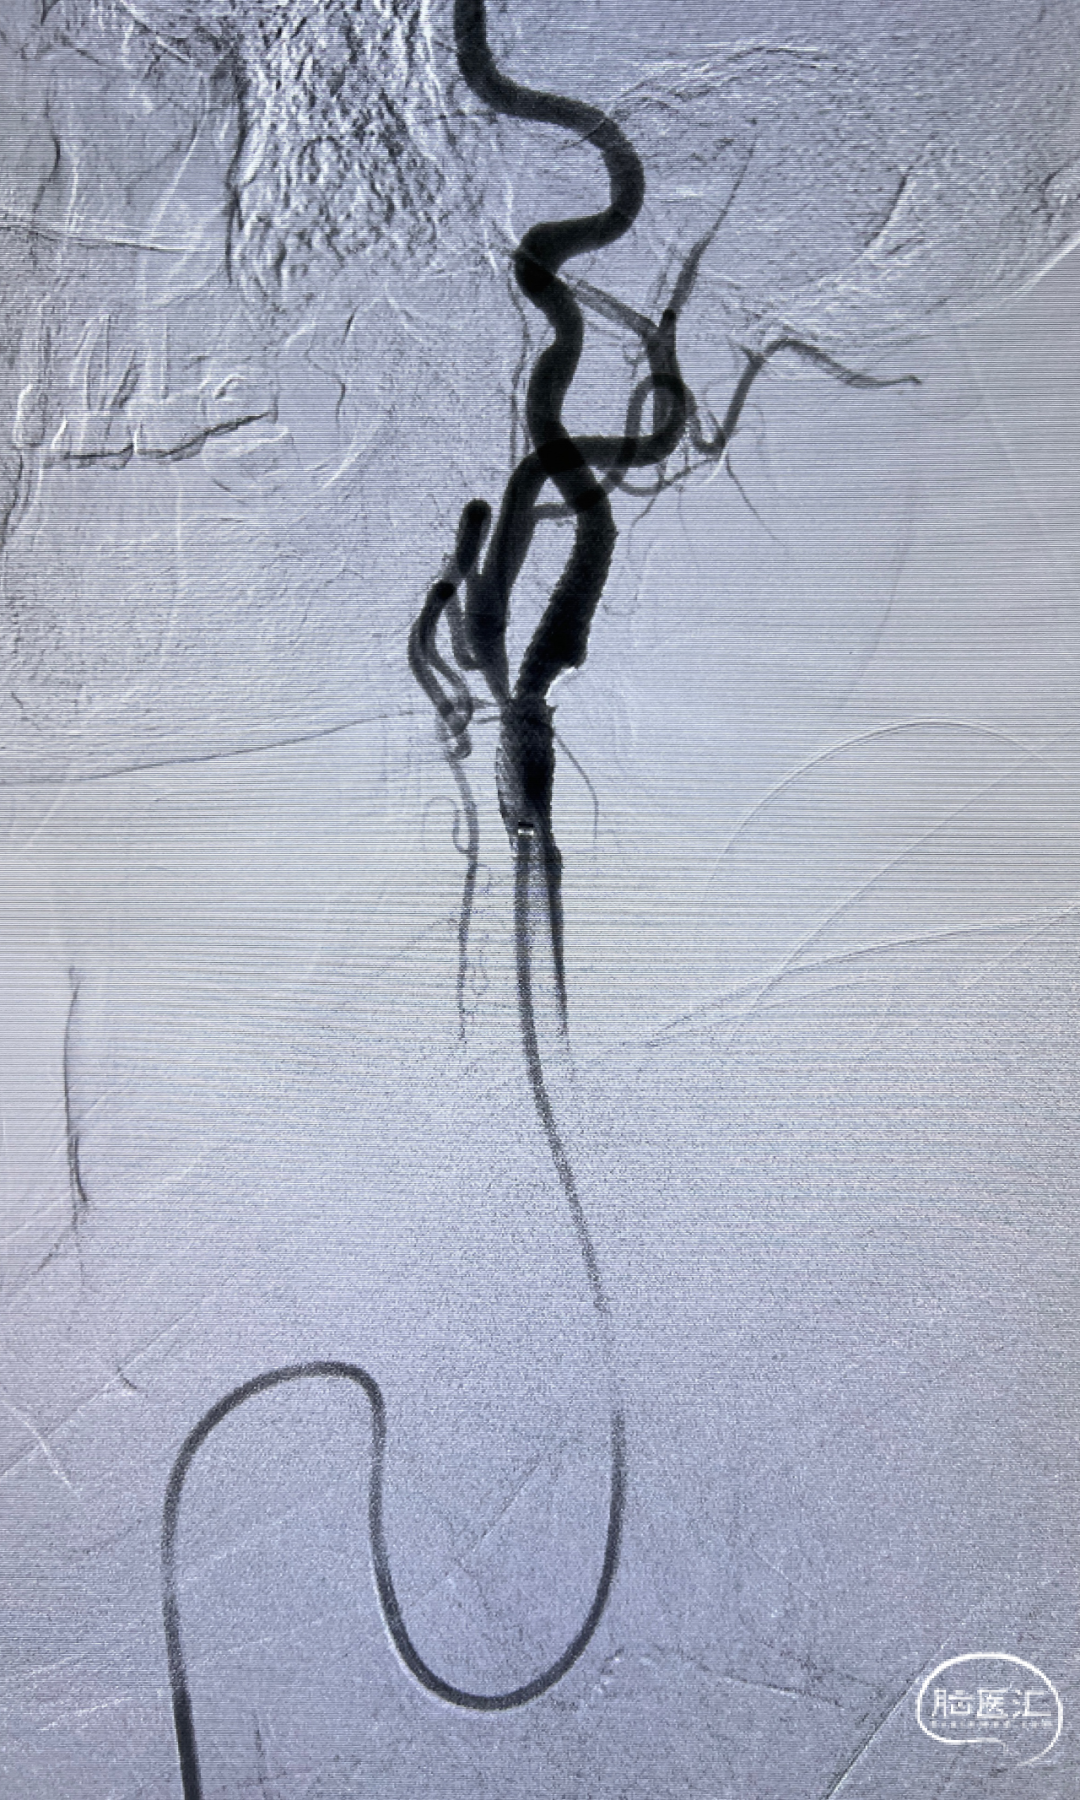

双侧股动脉造影:双侧髂动脉支架迂曲,不能通过造影导管及导丝。

经桡入路完成全脑血管造影:主动脉弓。

右侧颈内动脉闭塞。

左侧颈内动脉重度狭窄,左侧大脑中动脉闭塞,通过前交通动脉向右侧大脑中动脉供血区代偿。

后循环造影。

通路建立:经右侧桡动脉近桡穿刺,在赛诺APEX TRA GC™ SIM2-130cm内管的指引下将赛诺APEX TRA™ 6F 95cm经桡远端通路导引导管送行到颈总动脉末端。

5mm保护伞顺利到位,系统稳定。

5×30mm 扩张球囊到位,球囊扩张过程系统稳定。

通路弓上系统稳定支撑, 8×40mm Precise自膨支架顺滑到位。

支架系统释放过程,系统稳定。

左侧颈内动脉正侧位造影,狭窄解除。